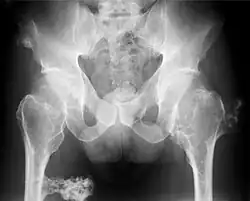

Mnogie kostniakochrzęstniaki (ang. multiple osteochondromas, hereditary multiple exostoses, HME, multiple hereditary exostoses, MHE, EXT, diaphyseal aclasis (multiple hereditary) osteochondromatosis, multiple cartilaginous exostoses) – uwarunkowana genetycznie choroba polegająca na wrodzonej predyspozycji do kostniakochrzęstniaków kości długich.

Osteochondromata pojawiają się i powiększają w pierwszej dekadzie życia, ich wzrost ulega zahamowaniu wraz z okresem dojrzewania. Zmiany są uszypułowane lub nie i bardzo zmiennej wielkości. Przeciętna liczba kostniakochrzęstniaków wynosi 15–18; może być ich mniej lub więcej, w zależności od rodziny i od pacjenta. Większość jest bezobjawowa. Kości, z których wychodzą zmiany, to kości długie, przede wszystkim kość udowa i kości podudzia. Kości twarzoczaszki nie są miejscem gdzie osteochondromata mogą się lokalizować. Objawy to ból i deformacje stawów, zwłaszcza w przypadku zmian zlokalizowanych w okolicy łokcia. Najistotniejszym powikłaniem jest złośliwienie zmian w kierunku chrzęstniakomięsaka, mające miejsce w 0,5–5% przypadków.

Rozpoznanie opiera się na badaniu klinicznym i radiologicznym oraz, o ile to możliwe, na histopatologicznej ocenie wycinka guza. Jeśli znane jest miejsce mutacji, technicznie możliwe jest zdiagnozowanie prenatalne choroby,